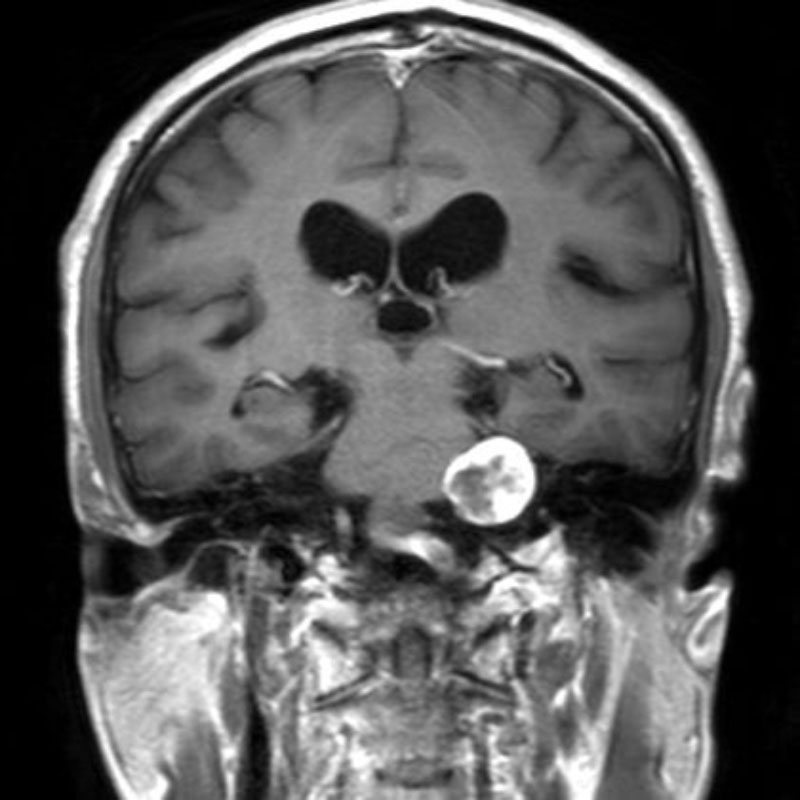

頭蓋内腫瘍摘出術

No.’23_52 手術前1

No.’23_52 手術前2

下垂体巨大腺腫